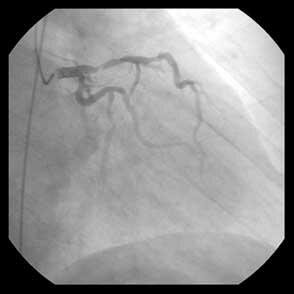

Fig.はpreの造影と、Thrombuster後のIVUS、post CBの造影です。

Pre-Spider